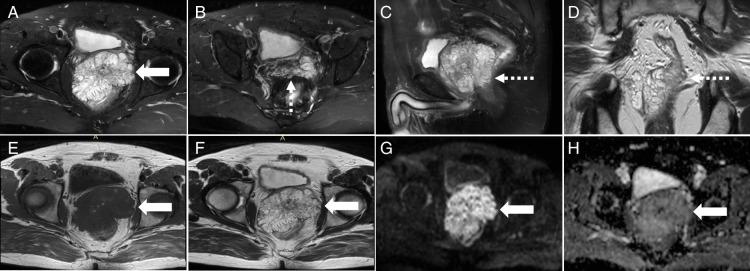

Primary prostate mucinous adenocarcinoma is an exceedingly rare entity with distinct imaging characteristics. We report the case of a 62-year-old man with biopsy-proven prostate mucinous adenocarcinoma. The patient underwent MRI and multi-tracer PET/CT. PET/CT images demonstrated the prostate lesion with moderate uptake of 68 Ga-PSMA and 68 Ga-FAPI, yet significantly high 18 F-FDG uptake. No abnormal radiotracers' uptake was observed elsewhere in the body. Multi-tracer PET/CT findings suggest that 18 F-FDG may be a more suitable radiotracer for the systemic assessment of primary prostate mucinous adenocarcinoma.

原发性前列腺黏液腺癌是一种极为罕见的疾病,具有独特的影像学特征。我们报告一例经活检证实为前列腺黏液腺癌的62岁男性病例。该患者接受了MRI和多示踪剂PET/CT检查。PET/CT图像显示前列腺病变对68Ga-PSMA和68Ga-FAPI有中度摄取,但18F-FDG摄取显著增高。身体其他部位未观察到放射性示踪剂的异常摄取。多示踪剂PET/CT检查结果表明,18F-FDG可能是对原发性前列腺黏液腺癌进行全身评估更合适的放射性示踪剂。